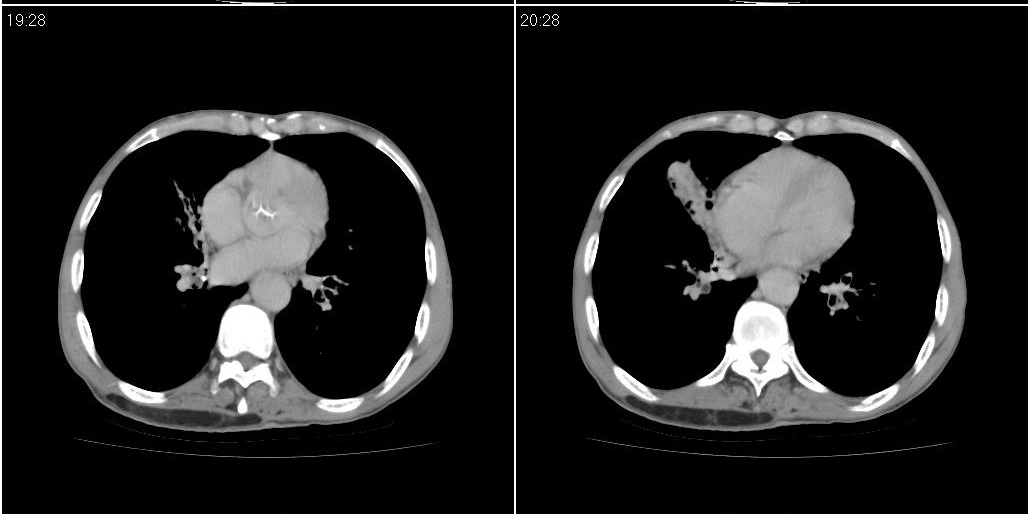

1)右肺中叶慢性炎症并支气管扩张,节段性肺不张。2)两肺下叶支气管扩张。

1)右肺中叶慢性炎症并支气管扩张,节段性肺不张。2)左肺下叶支气管扩张